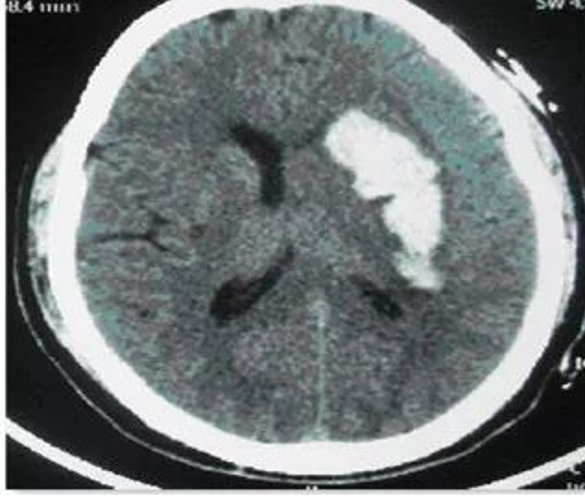

一名58岁男性患者,颈动脉狭窄行CEA手术,术后恢复良好,第五天准备拆线出院。然而在如厕时突发头痛、呕吐,CT检查显示脑出血,紧急行血肿清除术。

回顾该患者术后用药方案:利伐沙班10mg QD、拜阿司匹林100mg QD、氯吡格雷75mg QD、阿托伐他汀钙片20mg QN。这一病例引发我们对颈动脉手术围术期抗栓策略的深度思考。